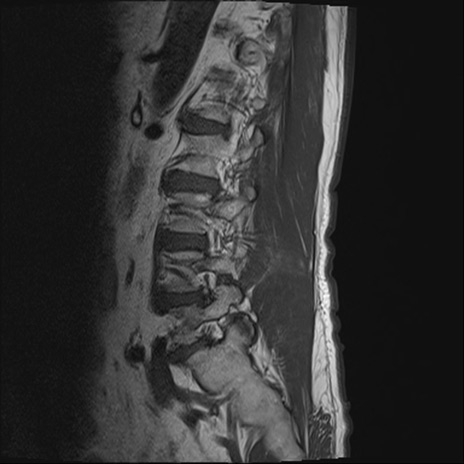

【整形】TIPS症例2 腰椎MRI T1WI(矢状断像)

【症例】70歳代男性

【主訴】左下肢痛

【現病歴】2週間前くらいから腰痛、左下肢痛あり。左臀部から大腿、下腿外側のしびれが常時ある。歩行とともに同部位の痛みあり。

【身体所見】Lasegue70-/60+、Bragard-/±、PTR ±/±、ATR -/-、IP 5/5、TA 5/4、TS 5/5、EHL 右第1足趾なし/3、FHL 5/5、hypersthesia(-)、足背動脈触知良好

異常所見と診断は?